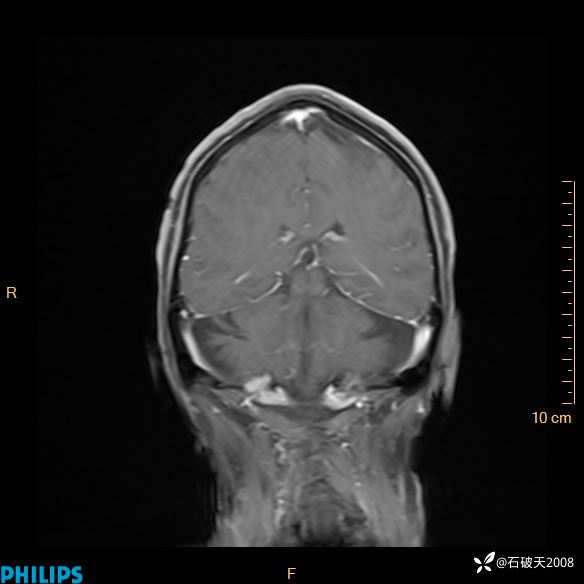

2024.2.21MR

增强冠状位